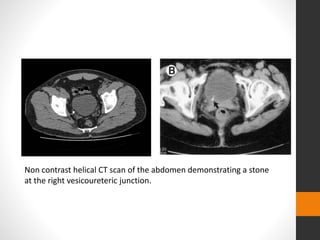

Non contrast helical CT scan of the abdomen demonstrating a stone

at the right vesicoureteric junction.